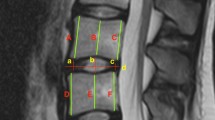

Additionally, the IVD was separated into five anatomical areas (posterior, left-lateral [L-lateral], right-lateral [R-lateral], anterior, nucleus pulposus [NP]) that represent the annulus fibrosus and nucleus pulposus footprints ideally (Fig. 2). Then, the 3D disc height of each area was measured as described above.

Pre-operative data of 3D disc height evaluated for each disc area showed that the anterior area was highest followed by the NP area, L-lateral area, R-lateral area and posterior area. Following LLIF surgery, the 3D disc height of all disc areas was significantly increased compared to that before surgery (P < 0.01 vs. Pre-op). However, there were no significant differences in the changes (Post-op data–Pre-op data) in 3D disc height among the five different disc areas. When the changes in 3D disc height were evaluated by the percentage of increase, no significant differences were also found among the five different areas.